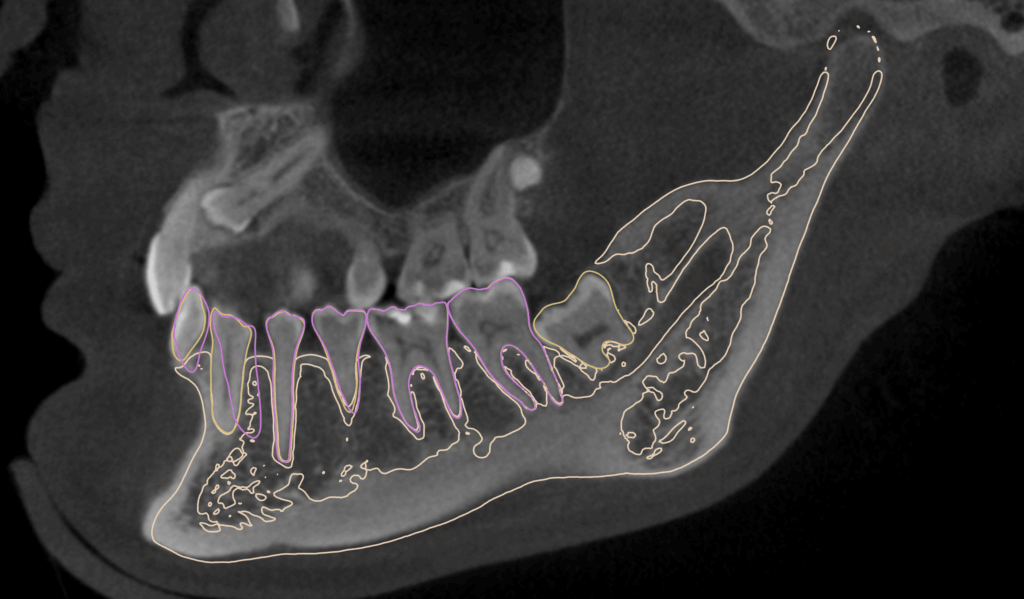

Reprezintă o simulare detaliată a poziției oaselor maxilare, a relațiilor dentare și a modului în care poate fi îmbunătățit profilul facial al pacientului.

Implică evaluarea atentă a structurii craniofaciale și a mușcăturii pacientului pentru a identifica problemele dentare și scheletice.

Această evaluare este crucială pentru a dezvolta un plan de tratament

eficient și personalizat.